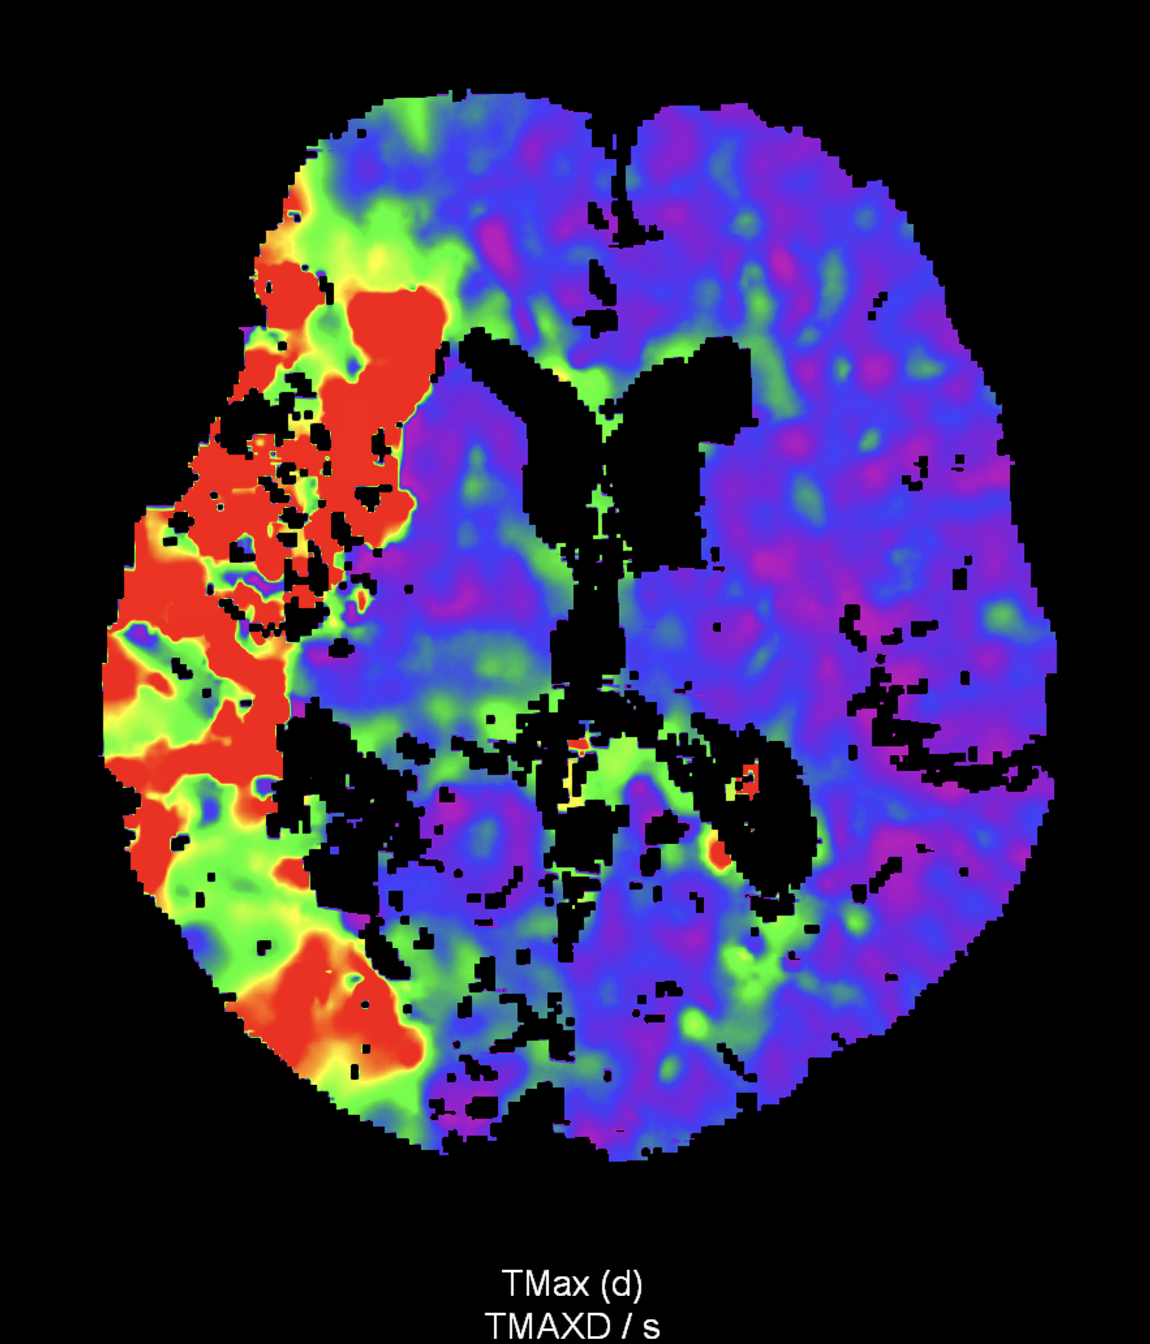

in patient chest pain, negative ECG but with elevated D-dimers was performed CTA of the chest to exclude highly suspected pulmonary embolism. No pulmonary embolism was see, but the pathology of the aortic arch and descending thoracic atorta. The images were consistent with aortic intramural hematoma type B according to the Stanford classification with incipient transformation in dissection – behind the subclavian artery, it is clear that the contrast agent is flowing into the intramural hematoma. Differentiation from wall thrombosis is facilitated by the presence of calcification in the detached intima, which is most clearly visible on virtual non-contrast imaging. The intramural hematoma itself exhibits different properties in terms of X-ray absorption. Coagulated blood is visible at the apex of the aortic arch, where it closely adjoins the area that is perfused and filled with contrast medium. There are other smaller areas filled with contrast medium at the sites of the intercostal arteries. These areas are secondary sites where the original intramural hematoma is channeled during its transformation into a classic aortic dissection.

Virtual non-contrast images help to distinguish between the intima and thus in the differential diagnosis of intramural hematoma versus wall thrombosis. Signs of fresh coagulated blood in IMH indicate bleeding into the aortic wall from the vasa vasorum. In contrast, monoenergetic images with lower energies of 40-55 keV highlight areas of intramural hematoma with active blood flow.

comparison of the the images 60, keV monoenergetic, virtual non-contrast (VNC), and iodine map images. The repercussion starts in the proximal tear of the intimate (the first three images), calcification in the intimate (next three images), tera at the level of the arising intercostal artery (last three images)

comparison of the sagittal aortic MPR in 40, 60, 140 and 190 keV monoenergetic images

comparison of the perpendicular planes to sagittal aortic MPR in 40, 60, 140 and 190 keV monoenergetic images